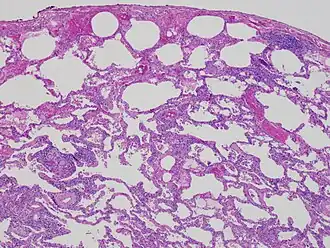

Allergische alveolitis (extrinsieke allergische alveolitis, allergische interstitiële pneumonitis, pneumoconiose door organisch stof) is een ontsteking in en rond de longblaasjes door een late allergische reactie op geïnhaleerd organisch stof of (minder vaak) chemicaliën.